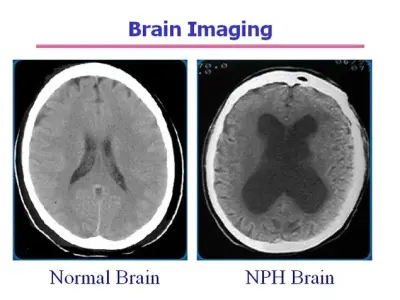

Normal Pressure Hydrocephalus (NPH) is a treatable cause of dementia in adults. Learn about the "wet, wobbly, and wacky" symptoms, NPH gait, and shunt surgery treatment.